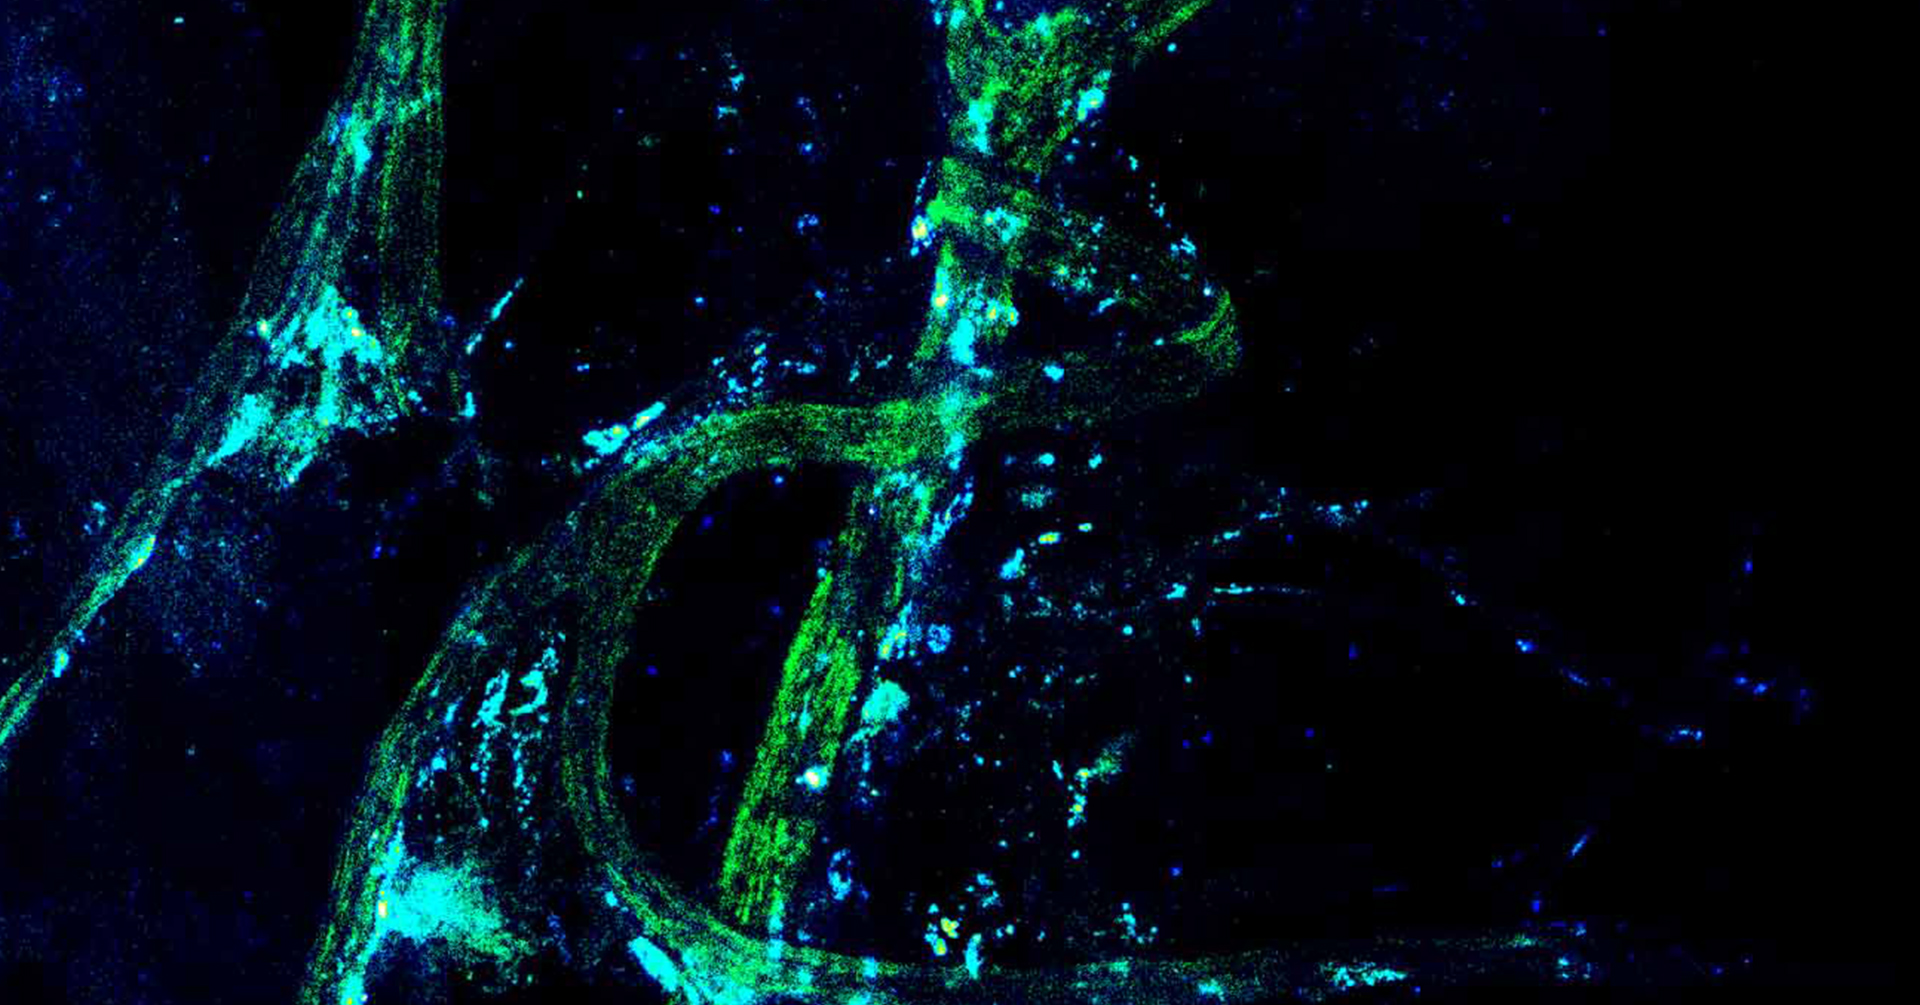

bolest